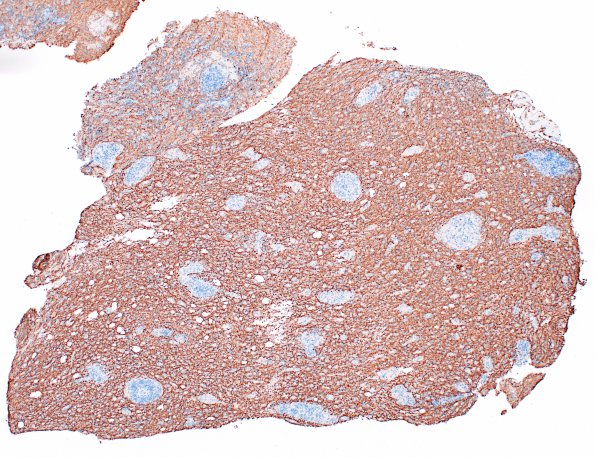

Washington University Experience | MISCELLANEOUS | Familial erythrophagic lymphohistiocytosis | 3D3 HLH, Perforin1 mutation (Case 3) NF 4X

All areas of the specimen, both central demyelination and perivascular peripheral regions have comparable preservation of axons (NF IHC)